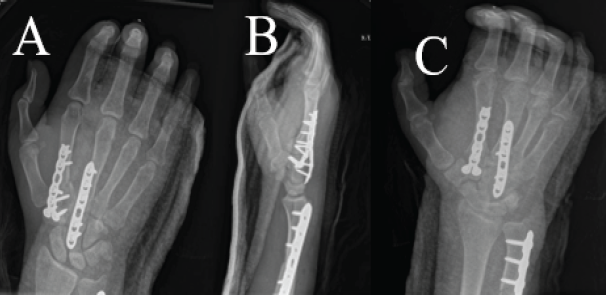

The patient was a 23-year-old right-hand dominant female preschool teacher who sustained a crush injury to the right hand and arm when she was riding in an ATV that rolled over. She was seen at a local trauma center and discharged in a splint. The patient presented to the clinic 3 weeks post-injury with complaints of numbness and tingling in the radial digits and diffuse swelling of the hand. Radiographs and a CT scan of the right hand were performed, which demonstrated right second and third CMC fracture dislocations, right fourth metacarpal base and capitate fractures, and a right displaced ulna shaft fracture (Fig. 1 and 2). There was also concern for acute carpal tunnel syndrome due to the numbness in the radial digits. Surgery was recommended for fixation of the second and third metacarpal fracture dislocations and capitate, as well as carpal tunnel release.

Figure 1: Pre-operative radiographs of the right hand in splint (a) oblique view, (b) lateral view, and (c) posteroanterior view. X-rays show second and third carpometacarpal base fracture dislocations, fourth metacarpal base and capitate fractures, and displaced ulna shaft fracture.